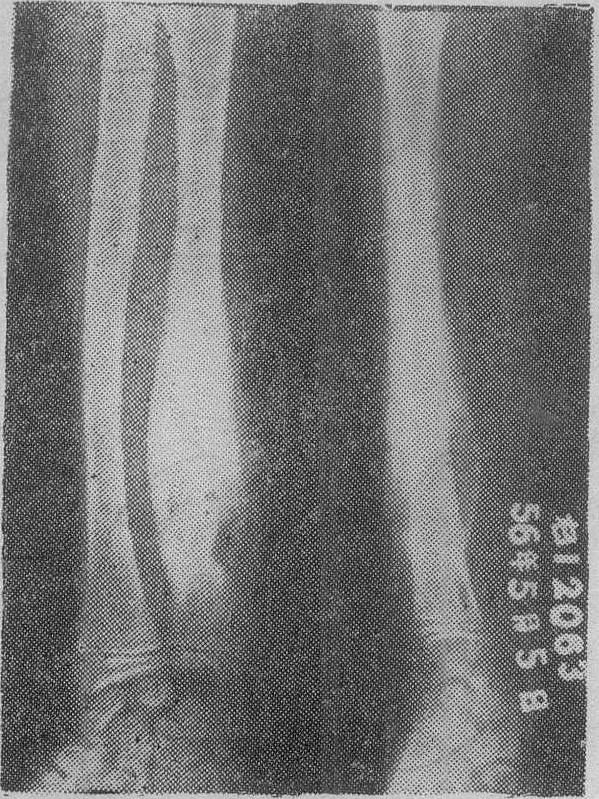

X线检查对本病非常重要。松质骨中心型结核早期可见局部骨小梁模糊是谓磨砂玻璃样改变,稍晚可见死骨游离,死骨一般呈椭圆形,密度比周围骨质稍高。死骨吸收后可见骨空洞,洞壁骨质稍致密(图1)。松质骨边缘型结核可见局限性溶骨性破坏,局部多无死骨或仅有细碎死骨,缺损边缘稍致密。密质骨结核可见髓腔内溶骨性破坏和骨膜新骨形成(图2)。干骺部结核则兼备松质骨和密质骨结核的特点(图3)。长期混合感染则骨质明显硬化。单纯滑膜结核仅见骨质疏松和局部软组织肿脓。早期全关节结核除局部骨质疏松和软组织肿胀外,尚可见关节小部分模糊或破坏。晚期全关节结核则关节边缘大部分模糊、破坏,关节间隙狭窄或消失,常合并脱位或畸形。除上述骨与关节改变外,有时尚能见到寒性脓肿影象,晚期脓肿可发生钙化。

图2 尺骨干密质骨结核可见多处溶骨性破坏及骨膜新骨形成

图3 肱骨上端干骺部结核

肱骨上端外侧可见溶骨性破坏,死骨形成及葱皮样骨膜新骨